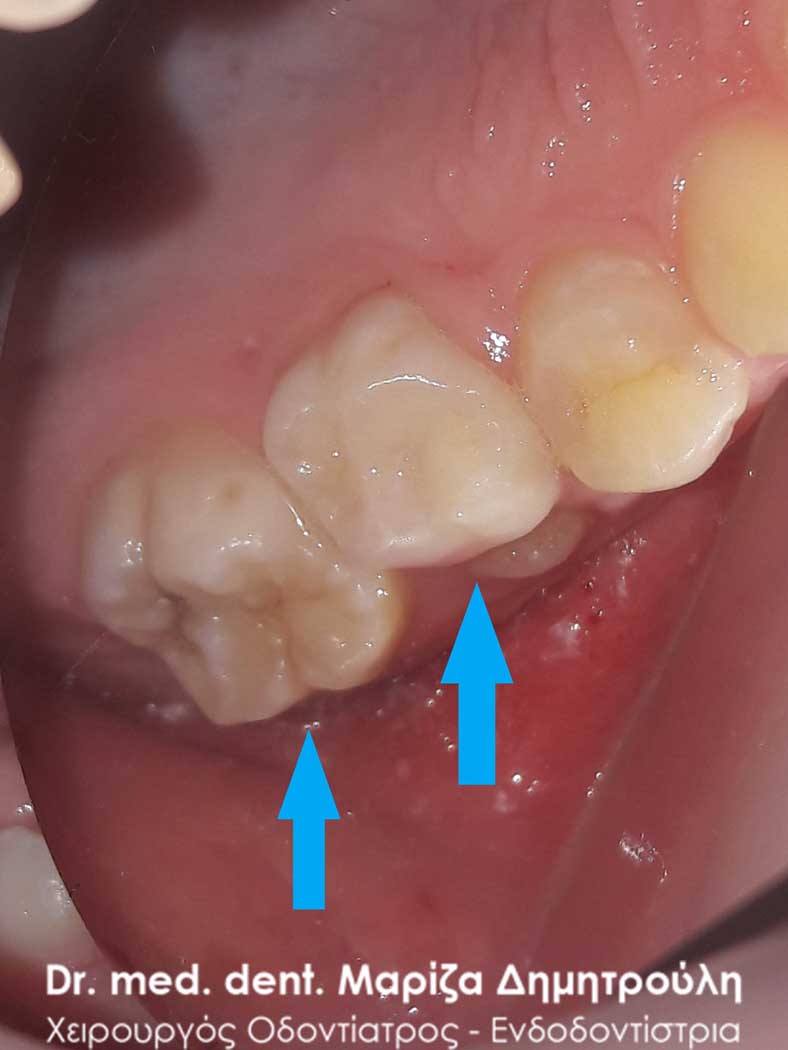

Η μικρή ασθενής επισκέφτηκε το ιατρείο με σκοπό την εξαγωγή του άνω πρώτου αριστερού νεογιλού γομφίου, ο οποίος παρέμενε στο στόμα παρόλο που είχε ανατείλει το αντίστοιχο μόνιμο δόντι. Εκτός από τα προαναφερθέντα, κατά την κλινική εξέταση, διαπιστώθηκε ο τερηδονισμός του άνω πρώτου μόνιμου γομφίου. Μετά τη χορήγηση της τοπικής αναισθησίας πραγματοποιήθηκε λευκό σφράγισμα στο μόνιμο γομφίο και ακολούθησε η εξαγωγή του νεογιλού δοντιού.

ΠΡΙΝ

ΜΕΤΑ